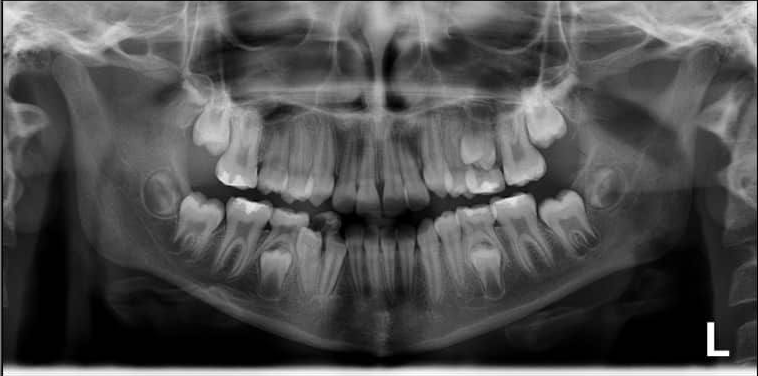

1. How old is the patient with the following X ray?